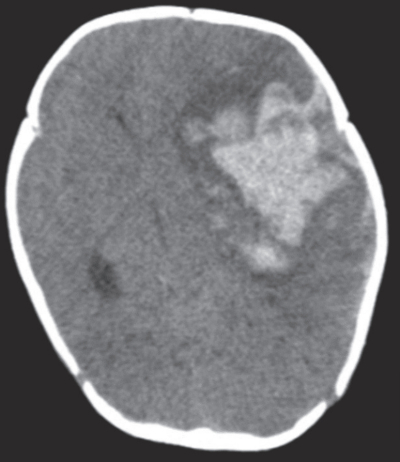

血液所見:赤血球 450万、Hb 9.5 g/dL、Ht 36%、白血球 10,800、血小板 25万、PT-INR 4.2(基準 0.9~1.1)、APTT 45.4秒(基準対照 32.2)、血液生化学所見:総蛋白 5.4 g/dL、アルブミン 3.3 g/dL、総ビリルビン 11.0 mg/dL、直接ビリルビン 6.8 mg/dL、AST 130 U/L、ALT 74 U/L、ALP 203 U/L(基準 114~339U/L)、γ-GT 410 U/L(基準 8~50U/L)、血糖 90 mg/dL。CRP 0.1 mg/dL。頭部CTを別に示す。